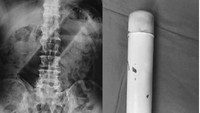

Pria 73 tahun mengeluh benjolan perut, dan operasi menemukan benda semacam botol silindris panjang di dalam kolon desenden. Benda asing dikeluarkan lewat pembedahan kolotomi. (Foto: Malaysia Family Physician)